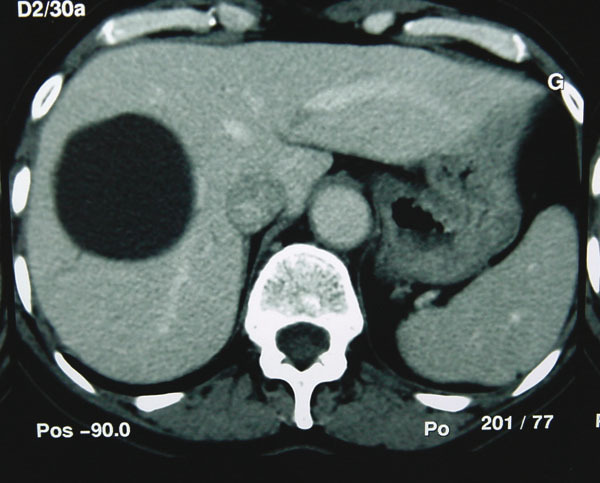

Il s’agit d’une malformation très fréquente, rarement unique, qui peut être découverte chez plus de 1% des adultes avec une nette prédominance féminine.